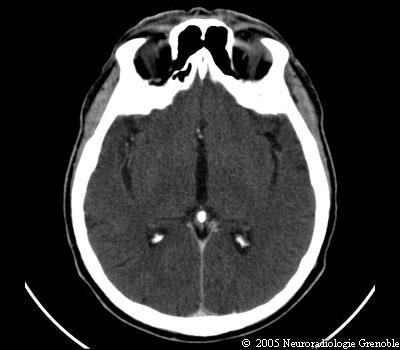

Radioanatomie TDM de l'encéphale

TDM cérébrale sans injection